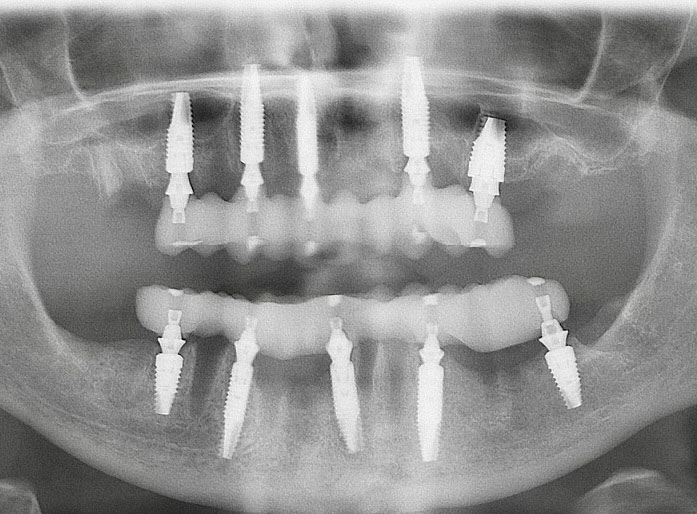

At the initial visit, a panoramic x-ray (Figure 11) and periapical x-rays were taken. The patient was photographed to capture her full face and shoulders, and a digital scan of the maxillary dentition was obtained. This file was electronically sent to the implant company to complete the VSD.

Fig 11. Initial panoramic radiograph.

Fig 21. Postoperative panoramic radiograph on the day of surgery.

Fig 22. Postoperative periapical x-rays on the day of surgery demonstrating the provisional restoration with ti-bases fully seated to multi-unit abutments and ideal immediate implant placement.